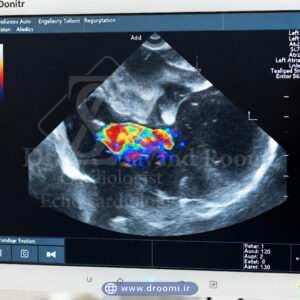

تصویر واقعی اکو داپلر رنگی قلب